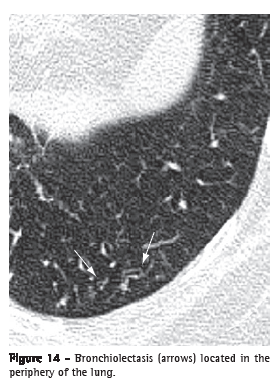

Bronchiolectasis (bronquiolectasia)Bronchiolectasis refers to the dilatation of a bronchiole. It is analogous to bronchiectasis, but it affects an airway of much smaller diameter, identified in the periphery of the lung (Figure 14). Bronchiolectasis manifests as rounded or tubular structures, generally located in the periphery of the lung, with thick walls or filled with secretion (see also Tree-in-bud pattern).(3,7) It can also be combined with other pulmonary opacities and to the distortion of the parenchyma in cases of fibrosis.

See also Traction bronchiectasis and traction bronchiolectasis.